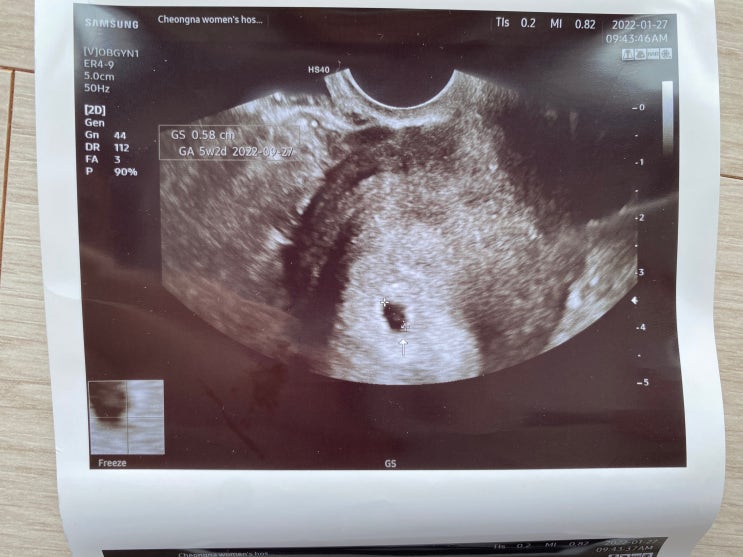

청라여성병원 제왕절개 후기

잊기전에 써내려가는 제왕절개 후기 분만예정일 9월 30일 그로부터 한달쯤 전에 분만의 방법에 대하여 생각...